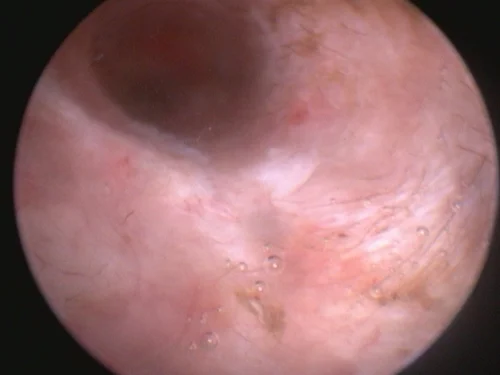

Video otoscopy has revolutionized the treatment of ear infections by our medical team as it provides amazing clarity to assess the condition of the ear canal, eardrum, and, at times, the middle ear.

Video otoscopy is the use of a small rigid otoscope with a camera built in that can be passed into the ear canal. The image is then projected onto a screen allowing magnification and much greater clarity to observe the deeper ear canal and structures.

Small channels within the otoscope also allow instruments to be passed into the ear canal to facilitate deeper cleaning, polyp or tumor removal, and other procedures. The use of video otoscopy in a challenging ear case is often the difference between months of continued struggles and a much more rapid resolution of infection and disease.